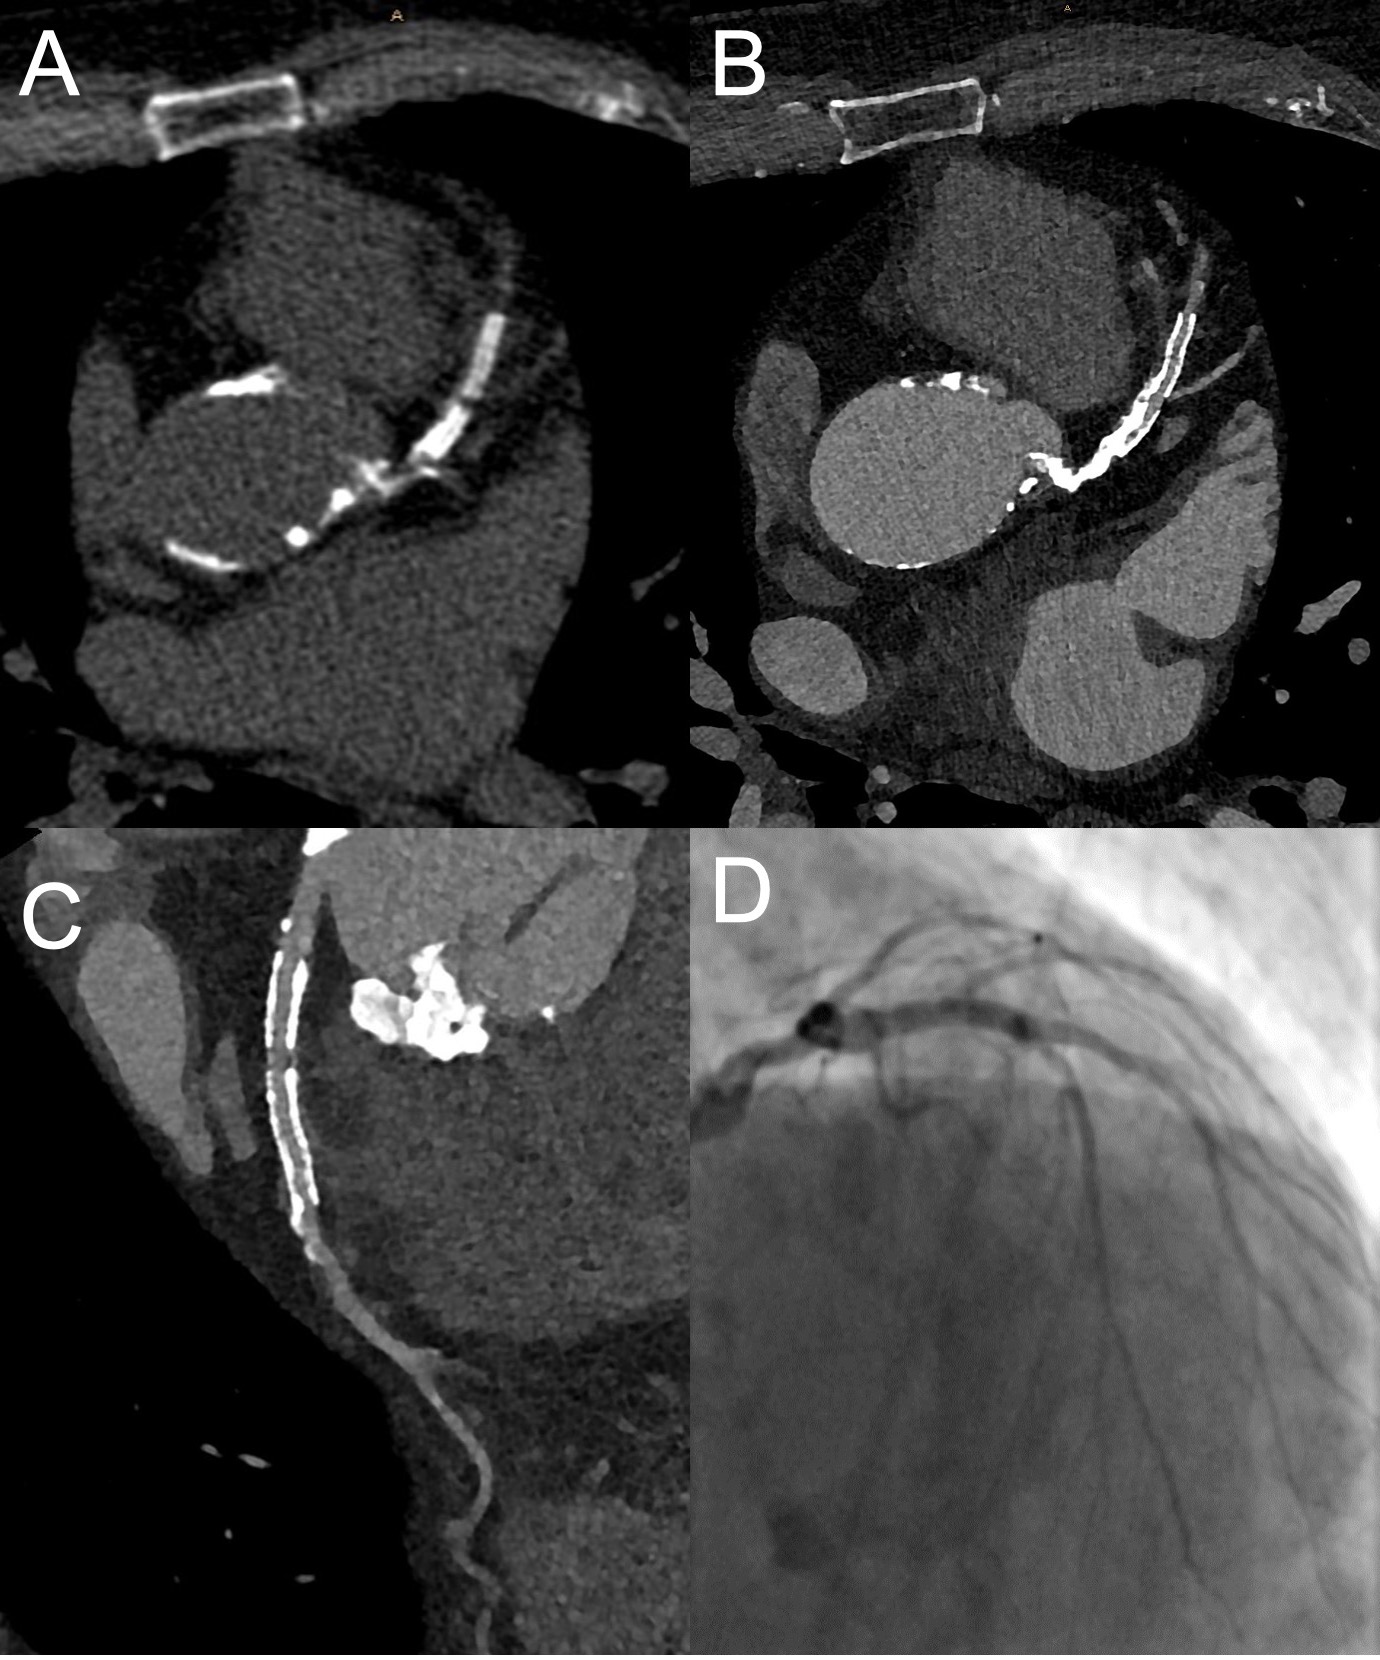

The most recent step in hardware advances for cCTA is the so-called photon-counting CT. It uses photon-counting detectors that separately register the energy of each photon. These offer a smaller pixel size and do not require the coating of each detection pixel by an optical reflector, which accounts for a 2- to 3-fold higher resolution than conventional CT (approximately 250 µm). In a recent clinical study photon-counting coronary CT led to significantly improved image quality (detectability indexes 2.3-fold to 2.9-fold higher) at a comparable radiation dose in 14 patients who underwent both standard energy-integrating detector dual-layer cCTA and photon-counting CT [47]. These results are promising since the higher resolution allowed for the visualization of smaller coronary vessels and the improved image quality was most evident in the presence of coronary stents and calcifications, which both are associated with impaired diagnostic image quality in standard cCTA. An example of a photon-counting cCTA scan is provided in Figure 2.

Figure 2. ECG-gated ultra-high-resolution cCTA of the heart using photon-counting. Images show the heart of a 79-year-old male patient referred for preprocedural planning of a transcatheter aortic valve replacement. Despite extensive calcifications (Agatston score of 3388) and two coronary stents in the LAD, a visualization of the coronary arteries was possible. (A): unenhanced coronary calcium scoring CT, axial reconstructions with a slice thickness of 2.0 mm using the Br36 kernel. (B): ultra-high-resolution cCTA, axial reconstructions with a slice thickness of 0.4 mm and an increment of 0.2 mm using the kernel Bv56 and moderate iteration Q3. (C): Curved multi-planar reconstruction of the LAD. An in-stent stenosis can be ruled out. (D): Invasive coronary angiography of the LAD confirming the CT findings. Courtesy of Christopher L. Schlett, University of Freiburg, Germany.